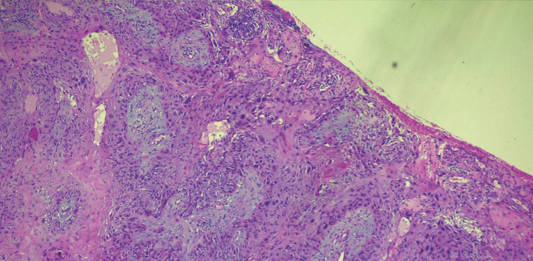

Oncologia oculare pediatrica: approccio clinico, ecografico e diagnosi differenziale in un...

L'oncologia oculare pediatrica rappresenta una sfida diagnostica per l’oftalmologo e il pediatra. Questo articolo descrive un caso...